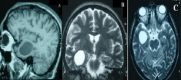

Our study aimed to highlight the role of cross sectional imaging techniques (CT, MRI) in positive diagnosis and post-therapeutic follow-up of cerebral hydatid cysts in children as well as to describe the peculiarities and the difficulties encountered in the management of these cysts based on our experience about 15 cases. We conducted a retrospective study of 15 cases of cerebral hydatidosis in children whose data were collected over a period of 10 years. CT scan of the brain with 5 mm slice thickness without and with injection of contrast product was performed in 15 patients. One patient underwent brain MRI creating either T1-weighted or T2-weighted images in all three planes without Gadolinium injection. The average age of patients was 9 years. Clinical symptoms were dominated by intracranial hypertension syndrome. Hydatid cyst was solitary and was located in the supratentorial level with an important mass effect on the ventricular system and the median line in most cases. All patients underwent surgery and patients’ evolution was favorable in all cases. CT scan is the test of choice for the diagnosis and the postoperative follow-up of patients with cerebral hydatid cysts. MRI is used essentially in the diagnosis of multiple and atypical type of cerebral hydatid cysts, enabling the design of more effective treatment strategy.